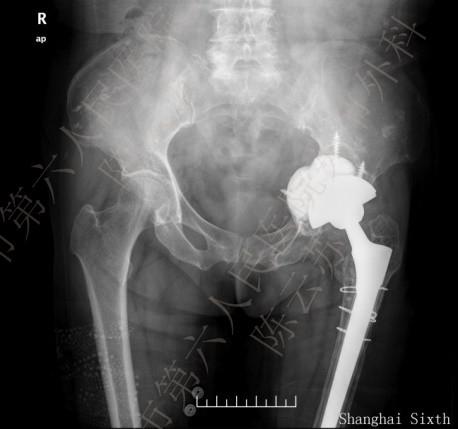

采用个性化人工垫块重建髋臼周围骨缺损的两例患者,手术中及术后影像学检查均证实个体化人工垫块与髋臼面骨缺损匹配完全,固定牢靠,髋臼假体安放及螺钉置入位置及角度理想,无血管神经损伤等并发症出现。目前两例患者分别随访1年及六月,X光片复查臼杯及垫块均固定在位,周围骨组织长入良好。

图4

患者。女性,65岁,左全髋关节置换术后18年,疼痛12年,加剧2年。图1:术前,图2:CT模拟设计,图3:3D打印模块,图4:术中缺损填充,图5:术后片,图6:术后1年随访片